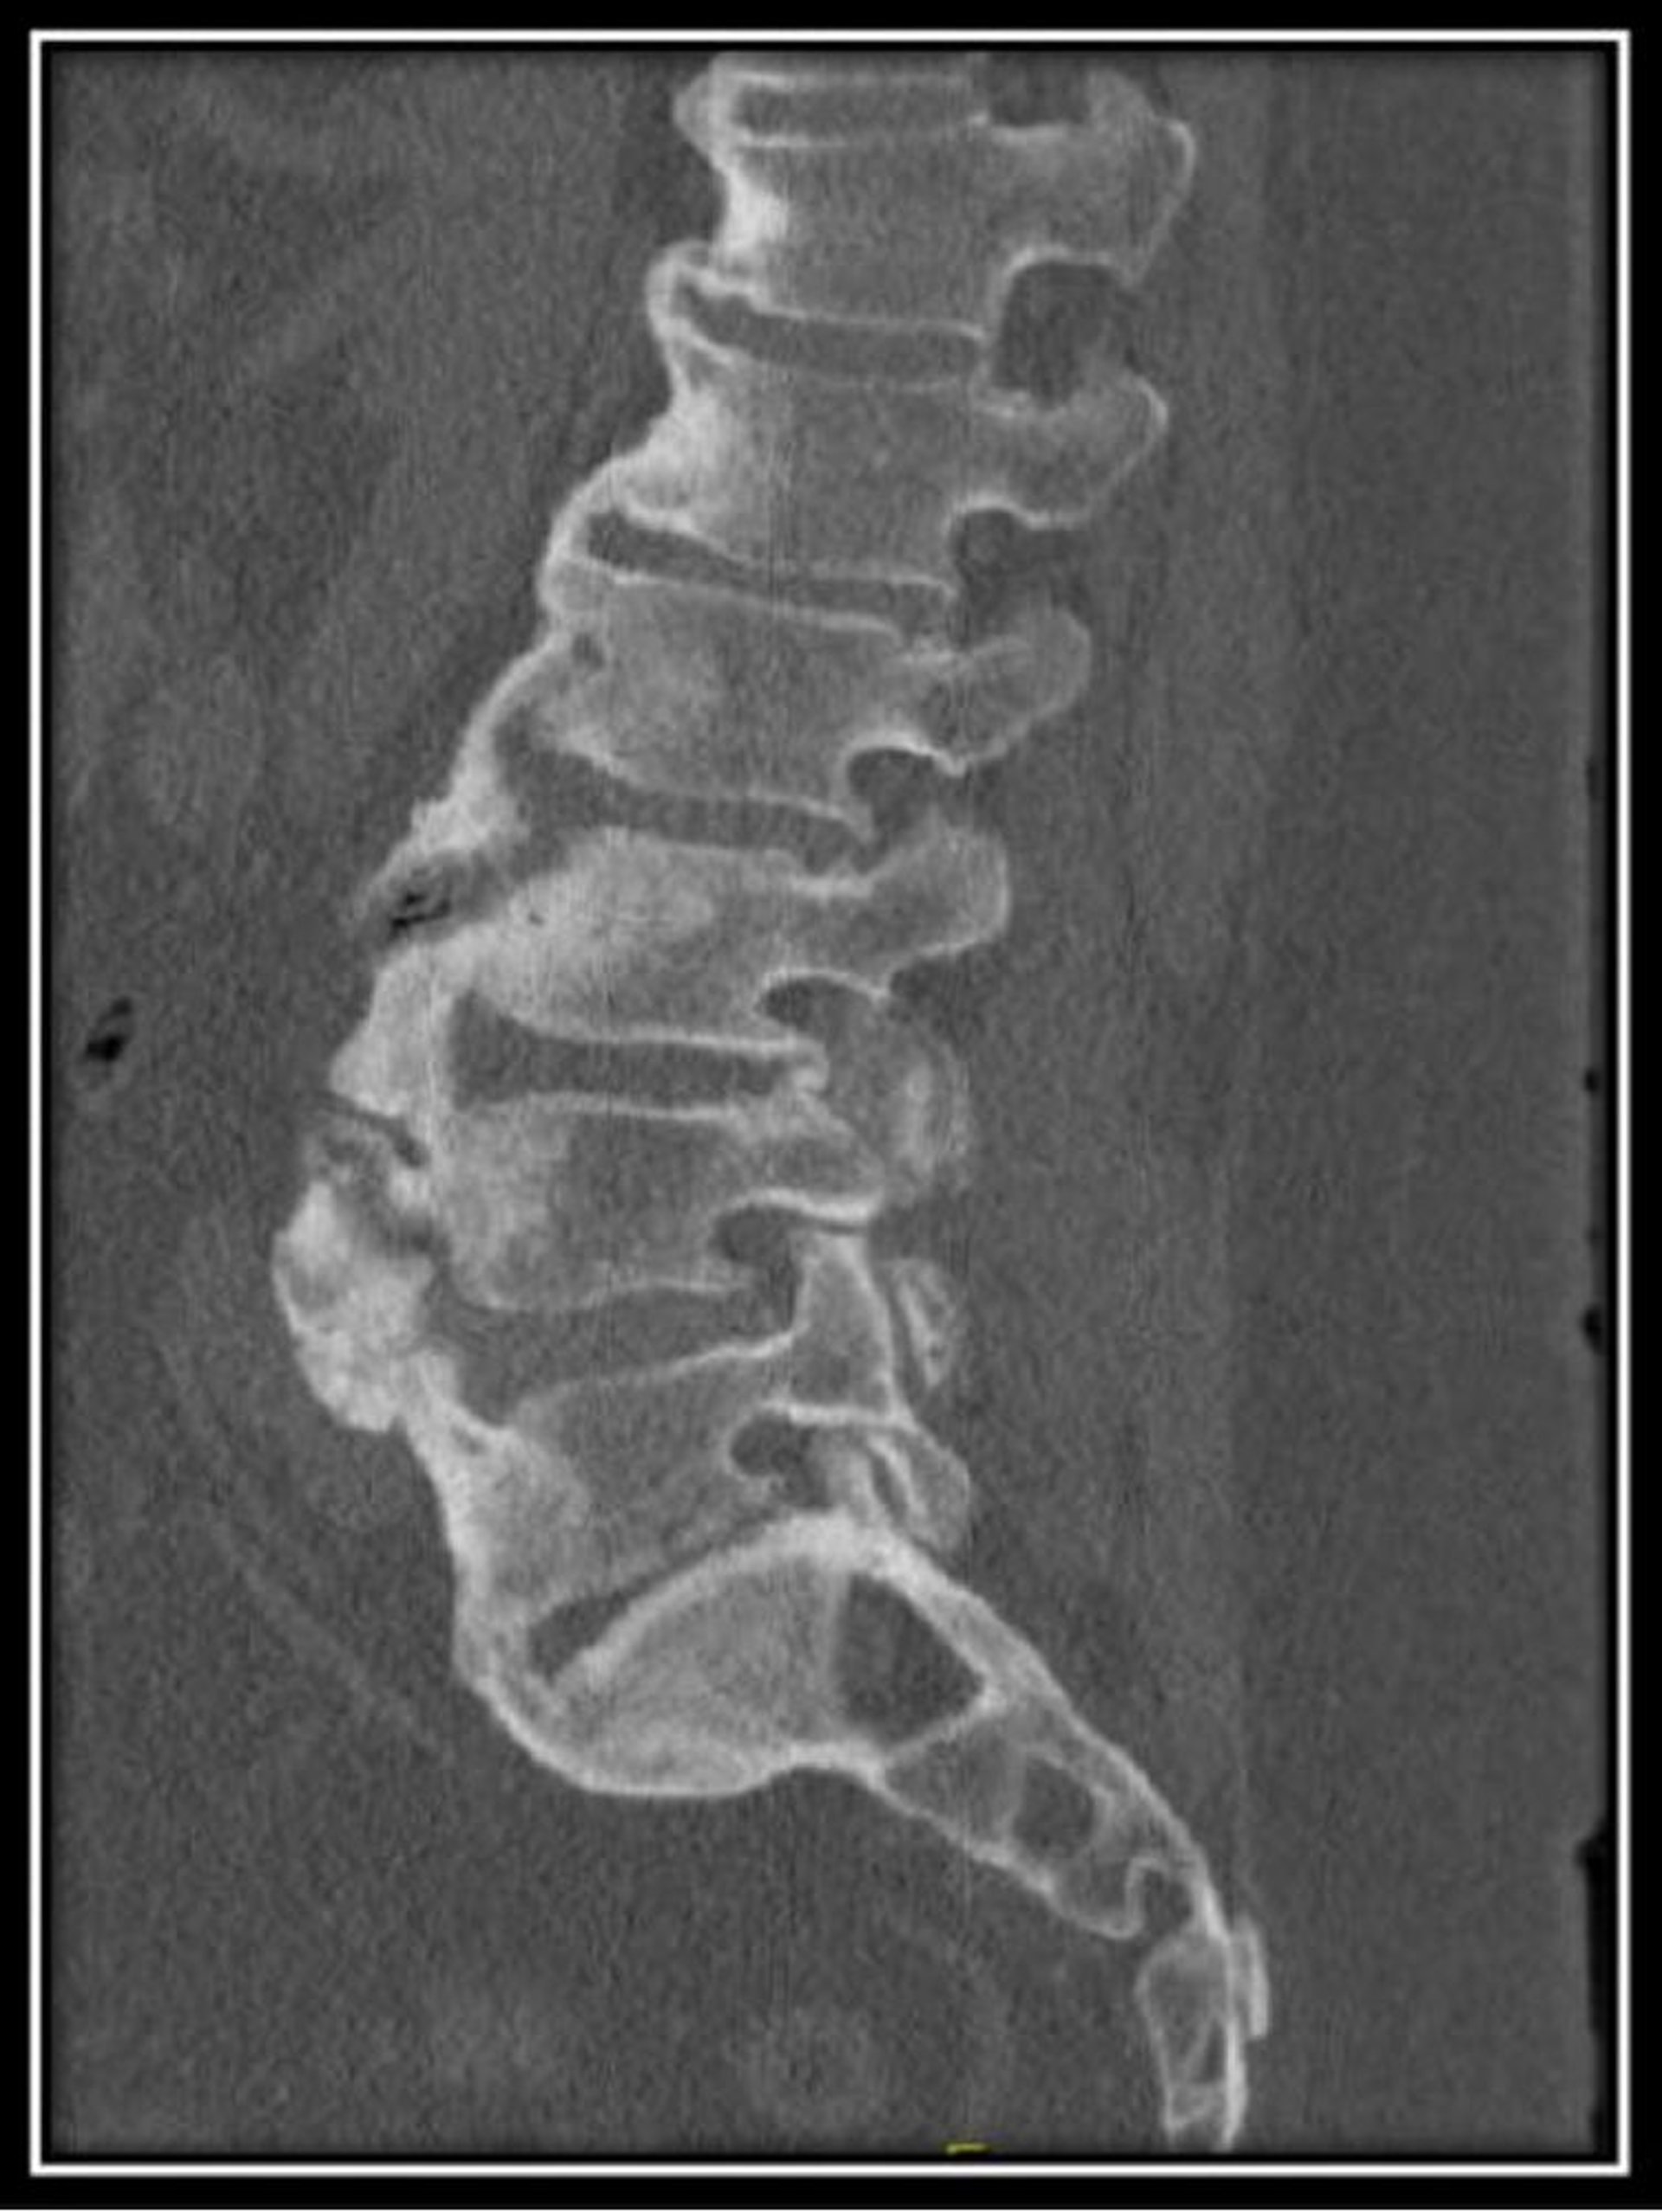

Дифузний ідіопатичний скелетний гіперостоз (КТ)

This CT scan of the lumbar spine in a patient with diffuse idiopathic skeletal hyperostosis shows normal vertebral body heights with diffuse anterior flowing osteophytes with maintained disc spaces.

Image courtesy of Kinanah Yaseen, MD.